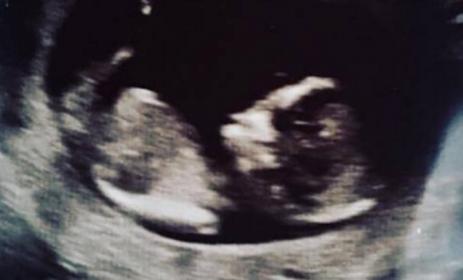

Does anyone have a nub theory based on this 13 week, 2 days shot? We're all hoping for a girl.

Attachment 34503